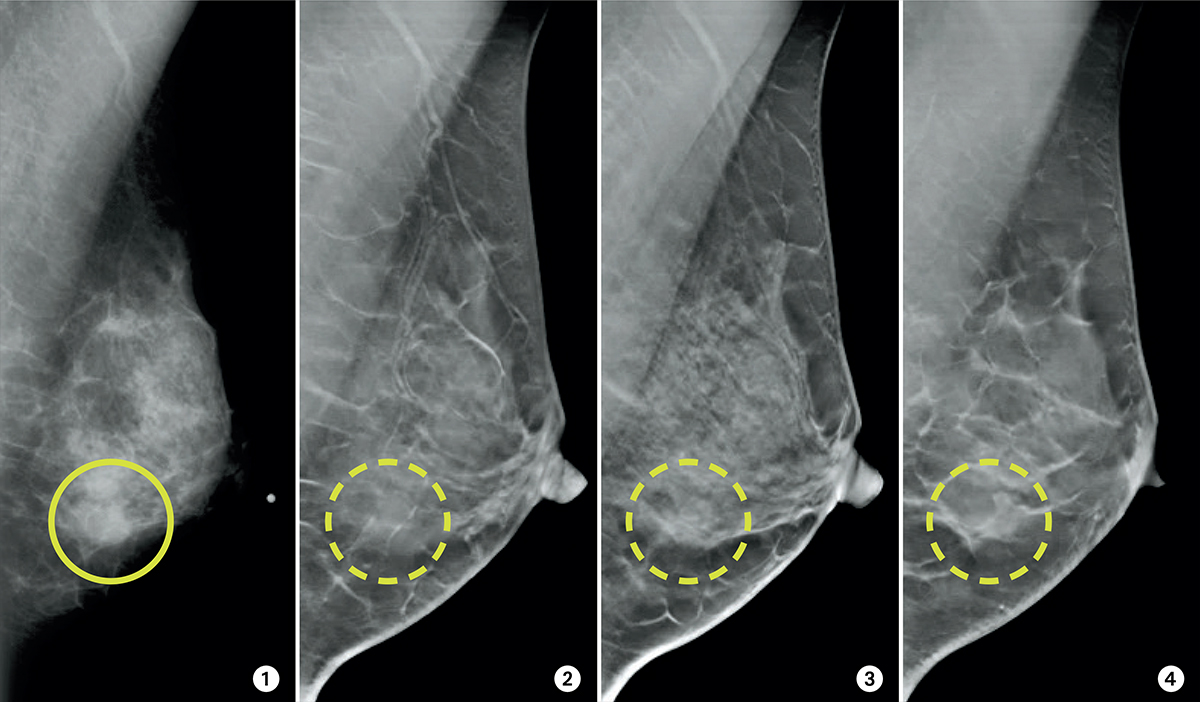

La mastografía es el estudio de imagen más utilizado para la detección temprana del cáncer de mama. Sin embargo, a lo largo del tiempo han surgido diversos mitos en torno a su efectividad, seguridad y utilidad en la prevención de enfermedades mamarias. Es fundamental conocer la información basada en evidencia científica para desmentir creencias erróneas y fomentar la detección oportuna.

La mastografía es el estudio de imagen más utilizado para la detección temprana del cáncer de mama. Sin embargo, a lo largo del tiempo han surgido diversos mitos en torno a su efectividad, seguridad y utilidad en la prevención de enfermedades mamarias. Es fundamental conocer la información basada en evidencia científica para desmentir creencias erróneas y fomentar la detección oportuna. La tomografía computarizada (TC) es una de las herramientas más avanzadas y eficaces utilizadas en la medicina para obtener imágenes detalladas del interior del cuerpo humano. A través del uso de rayos X y procesamiento computarizado, esta técnica permite a los médicos diagnosticar una amplia variedad de enfermedades y condiciones. Sin embargo, como con cualquier procedimiento médico, es natural que los pacientes tengan preguntas sobre el examen. Este artículo aborda las preguntas más frecuentes sobre la tomografía computarizada, ofreciendo información clara y precisa.